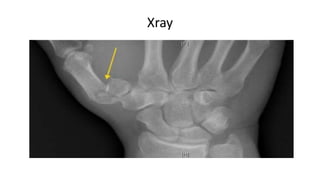

Radiographic Evaluation

•Xray – posteroanterior and

Lateral radiograph